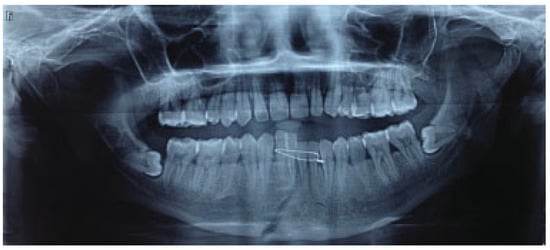

The mean for ramal height shortening was found to be 11.9 (0.99) preoperatively and 11.6 (1.57) postoperatively in Group A. It was compared using paired t-test and this difference was found not to be statistically significant (p = 0.34; Figure 1 and Figure 2). The mean for ramal height shortening was found to be 12.5 (0.84) preoperatively and (0.87) postoperatively in Group B. It was compared using paired t-test and this difference was found to be statistically significant (p < 0.05; Figure 3 and Figure 4).

Figure 3.

Group B: Preoperative orthopantomography showing left displaced subcondylar fracture and right parasymphysis fracture.